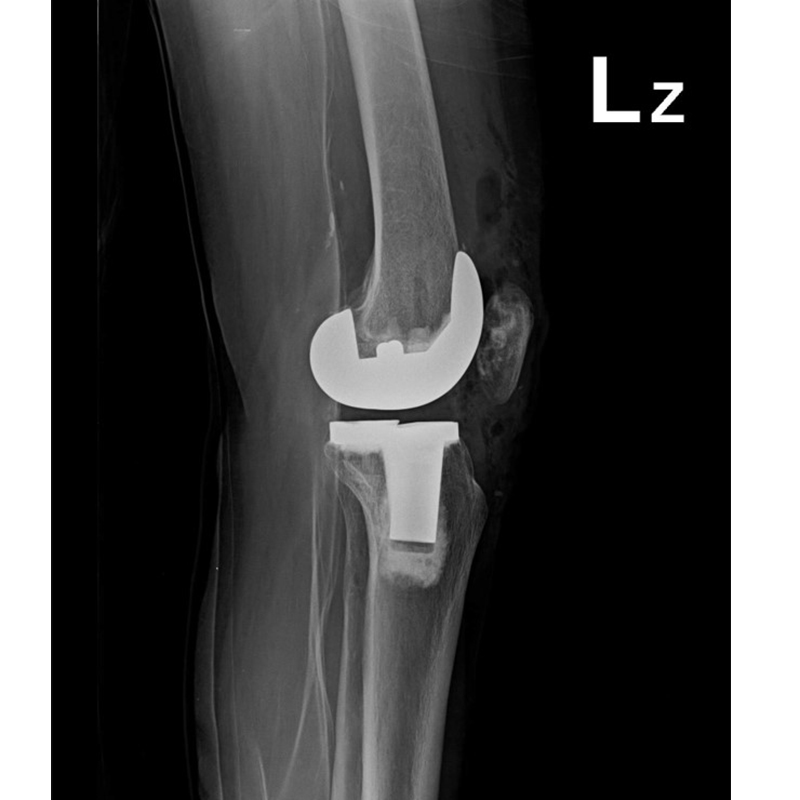

傳統全膝關節置換 首頁 案例分享 膝關節手術 傳統全膝關節置換 江女士 61歲 術前 術後 劉先生 83歲 術前 術後 70歲 柯先生 術前 術後 75歲 黃女士 術前 術後 77歲 羅女士 術前 術後